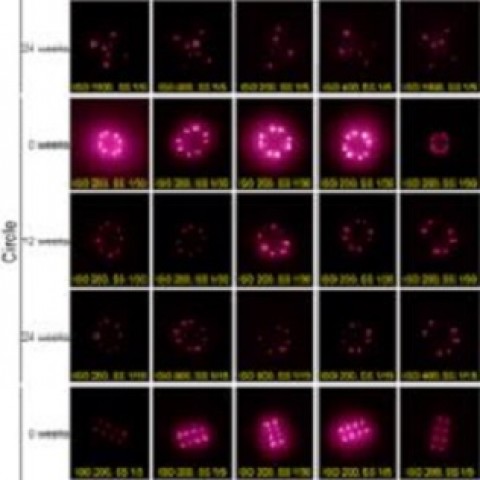

O segundo invento biotecnológico que desponta para ser utilizado massivamente é a “tatuagem quântica”, os QDs NIR (near-infrared quantum dots - NIR QDs), ou pontos quânticos luminescentes (QDs) no infra-vermelho próximo (NIR). A luz NIR possui pequena interferência de fundo e grande profundidade de penetração, o que torna os QDs NIR vantajosos em aplicações de bio-imagem.

Pontos quânticos sob a pele podem guardar histórico de vacinação, além de formar desenhos bonitos (Foto: Divulgação Kevin J. McHugh MIT)

Pontos quânticos sob a pele podem guardar histórico de vacinação, além de formar desenhos bonitos (Foto: Divulgação Kevin J. McHugh MIT)

A invenção, que teria por finalidade rastrear a cobertura de vacinas de cada cidadão, padronizando registros de imunização e possibilitando rastrear a cobertura de vacinas em todo o mundo, funciona da seguinte forma: adesivos de microagulhas intradérmicas, de micropartículas emissoras de luz no infravermelho próximo à pele, injetam uma vacina em código; o padrão de partículas na pele pode servir como um registro de vacinação em cada pessoa. Em resumo: QDs intradérmicos podem ser usados para codificar informações com segurança e podem ser entregues com uma vacina. Os padrões de partículas são invisíveis aos olhos, mas podem ser visualizados usando smartphones modificados.

Sendo uma plataforma de codificação e detecção de informações intradérmicas, está capacitada para ser usada como instrumento de identificação, ainda que neste momento seja divulgado como algo benéfico à humanidade.

Um grupo de bioengenheiros no MIT (Instituto de Tecnologia Massachusetts) desenvolveu uma forma de armazenar o histórico de vacinação de um indivíduo em seu próprio corpo. Por meio de um adesivo com microagulhas, é possível inserir pontos quânticos sob a pele do cidadão. Qualquer pessoa com uma fonte de luz adaptada -- um smartphone, por exemplo -- consegue checar a "mensagem" deixada.

"Começamos pensando em usar uma tinta invisível a olho nu", afirmou Ana Jaklenec, cientista no Instituto Koch de Pesquisa Integrada de Câncer, do MIT, em entrevista à IEEE Spectrum. A equipe acabou chegando a outra solução, o uso de pontos quânticos. Esses pontos agregam nanopartículas de semicondutores, com 2 a 10 nanômetros (1 milímetro é um milhão de vezes maior que um nanômetro). Eles podem absorver luz em um comprimento de onda e fazer a conversão para outro comprimento -- ou seja, absorver luz de uma cor e emiti-la em outra, ou emitir luz que seja visível somente em condições específicas. Por isso, vêm sendo usados em televisores, monitores variados, paineis solares e sensores biológicos.

Na experiência, publicada na quarta-feira (18/12) no Science Translational Medicine, a equipe do MIT uso adesivos com microagulhas para depositar os pontos sob a pele de cobaias e depois conseguiu reconhecer a mensagem com uso de um smartphone, alterado para detectar luz quase infravermelha, invisível a olho nu. Os testes foram feitos também com corpos humanos de vários tons de pele. A mensagem persistiu por nove meses. Os cientistas acreditam que, no estágio atual da pesquisa, a mensagem se mantenha estável por cinco anos.

Pesquisadores liderados por uma equipe do Instituto de Tecnologia de Massachusetts (MIT) criaram uma plataforma de microagulhas usando micropartículas fluorescentes chamadas pontos quânticos (QD), que podem fornecer vacinas e, ao mesmo tempo, codificar invisivelmente o histórico de vacinas diretamente na pele. Os pontos quânticos são compostos de nanocristais, que emitem luz infravermelha próxima (NIR) que pode ser detectada por um smartphone especialmente equipado. Testes usando a plataforma mostraram que QDs entregues a amostras de pele humana ainda eram detectáveis após fotodegradação que simulavam cinco anos de exposição à luz solar e permaneceram detectáveis por até nove meses quando testados em ratos.

Há vários anos, a equipe do MIT decidiu criar um método para registrar informações de vacinação de uma maneira que não requer um banco de dados centralizado ou outra infraestrutura. Para criar um registro médico descentralizado "em paciente", os pesquisadores agora desenvolveram um novo tipo de ponto quântico à base de cobre, que emite luz no espectro infravermelho próximo. Os pontos têm cerca de 4 nm de diâmetro e são encapsulados em micropartículas biocompatíveis que formam esferas com cerca de 20 µm de diâmetro. Esse encapsulamento permite que o corante permaneça no lugar, sob a pele, após a injeção.

Ao carregar seletivamente micropartículas nas microagulhas, os adesivos proporcionam um padrão na pele invisível a olho nu, mas podem ser digitalizados com um smartphone que remove o filtro infravermelho. O adesivo pode ser personalizado para imprimir diferentes padrões que correspondem ao tipo de vacina entregue. Testes usando pele de cadáver humano mostraram que os padrões de pontos quânticos poderiam ser detectados pelas câmeras dos smartphones após cinco anos de exposição solar simulada. Os pesquisadores também testaram a estratégia de vacinação em ratos, usando adesivos de microagulhas que liberavam os pontos quânticos junto com uma vacina contra a poliomielite. Eles descobriram que esses ratos geraram uma resposta imune semelhante à resposta de ratos que receberam uma vacina tradicional contra a poliomielite injetada.